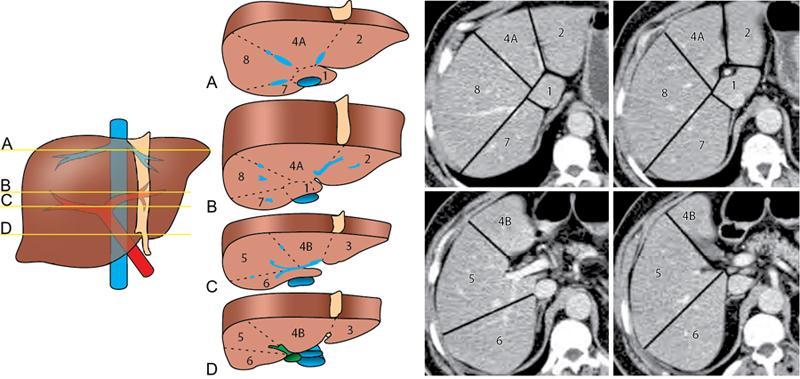

CROSS SECTIONAL ANATOMY OF ABDOMEN Satya Jha NORMAL ANATOMY OF ABDOMEN AND PELVIS Amandeep Singh The two major surfaces: The anterior and posterior layers of the coronary ligament converge on bare area (not covered by peritoneum). Its right and left margins form the right and left triangular ligaments. The right triangular ligament extends toward the diaphragm and separates right subphrenic space from right subhepatic space. The left triangular ligament gives tracts extending to the diaphragm and falciform ligament and does not compartmentalize the left subphrenic space. Ligamentum teres or the obliterated umblical vein is contained in falciform ligament which attaches the liver to anterior abdominal wall. The main portal vein, the proper hepatic artery and the common bile duct are contained within investing peritoneal folds of hepatoduodenal ligament at the porta hepatis (Fig. 7.2.2.1). Liver is divided into eight segments which are functionally independent and have their own vascular supply and biliary drainage. Arterial circulation: The branches of the hepatic artery accompanying the portal veins. Hepatic venous system: The right, middle, and left hepatic veins draining into IVC (Figs. 7.2.2.2 and 7.2.2.3). The gallbladder is a blind pear-shaped muscular membranous sac which is an embryologic derivative of the foregut, is a pouch lying along the undersurface of the liver. The gallbladder fossa is located in the plane of the interlobar fissure, which lies between the right and left hepatic lobes. Its major function is to store and concentrate bile which is produced by the liver. It measures approximately 4 cm in diameter when it is normally distended. Gallbladder is a smaller tubular structure in contracted state. The normal gallbladder wall thickness ranges from 1 to 3 mm. The gallbladder is divided into the fundus, body and neck. Infundibulum is present in the region of neck of the gallbladder, which is called the Hartmann pouch, where gallstones are usually impacted. Intrahepatic biliary radicles (IHBRs) scattered throughout the liver get confluent towards the hilum. They unite to form the right and left main hepatic ducts which further unite to form common hepatic duct (CHD) at the hilum. Common bile duct is formed by the union of cystic duct with common hepatic duct. The main pancreatic duct is joined with the common bile duct to form the ampulla of Vater at the major duodenal papilla (Figs. 7.2.2.4 and 7.2.2.5). Pancreas is located in anterior pararenal space of retroperitoneum anterior to perirenal (Gerota’s) fascia and posterior to parietal peritoneum. It is divided into head, uncinate process, neck, body and tail from right to left. Pancreas lies anterior to portal vein, which marks the point of transition between the body and neck. The region between head of pancreas and second and third parts of duodenum is known as the pancreatic groove. In postnephrectomy cases or with agenesis of kidney or ectopic kidney, pancreas moves posteriorly to partially fill in the empty renal fossa; its soft tissue density should not be mistaken for recurrent tumour. It is located in the pancreatic groove and is bounded superiorly by the duodenal bulb, laterally by second portion of duodenum, inferiorly by third portion of duodenum, medially by superior mesenteric vein and anterior to inferior vena cava. It is a wedge or wedge shaped lying posterior to superior mesenteric artery and vein. It is an imaginary junction between the head and body and lies directly over the junction of the splenic vein and superior mesenteric vein. It is located posterior to the lesser sac and anterior to the aorta, left adrenal gland, left kidney, and renal vessels and runs obliquely upward to the left of the superior mesenteric vessels. It is situated median to the colonic flexure and anterior to the left kidney. It is located in close proximity to the splenic hilum without a notable relation with the body of pancreas. It is seen anterior to the left kidney and median to the colonic flexure. The distal part of the tail passes between the peritoneal layers of the splenorenal ligament (Fig. 7.2.2.6 and 7.2.2.7).

Liver

The bismuth and couinaud classification of liver

Couinaud

Traditional

Segment I

Caudate lobe

Segment II

Lateral superior segment of left lobe of liver

Segment III

Lateral inferior segment of left lobe of liver

Segment Iva

Medial superior segment of left lobe of liver

Segment IVb

Medial inferior segment of left lobe of liver

Segment V

Anterior inferior segment of right lobe of liver

Segment VI

Posterior inferior segment of right lobe of liver

Segment VII

Posterior superior segment of right lobe of liver

Segment VIII

Anterior superior segment of right lobe of liver